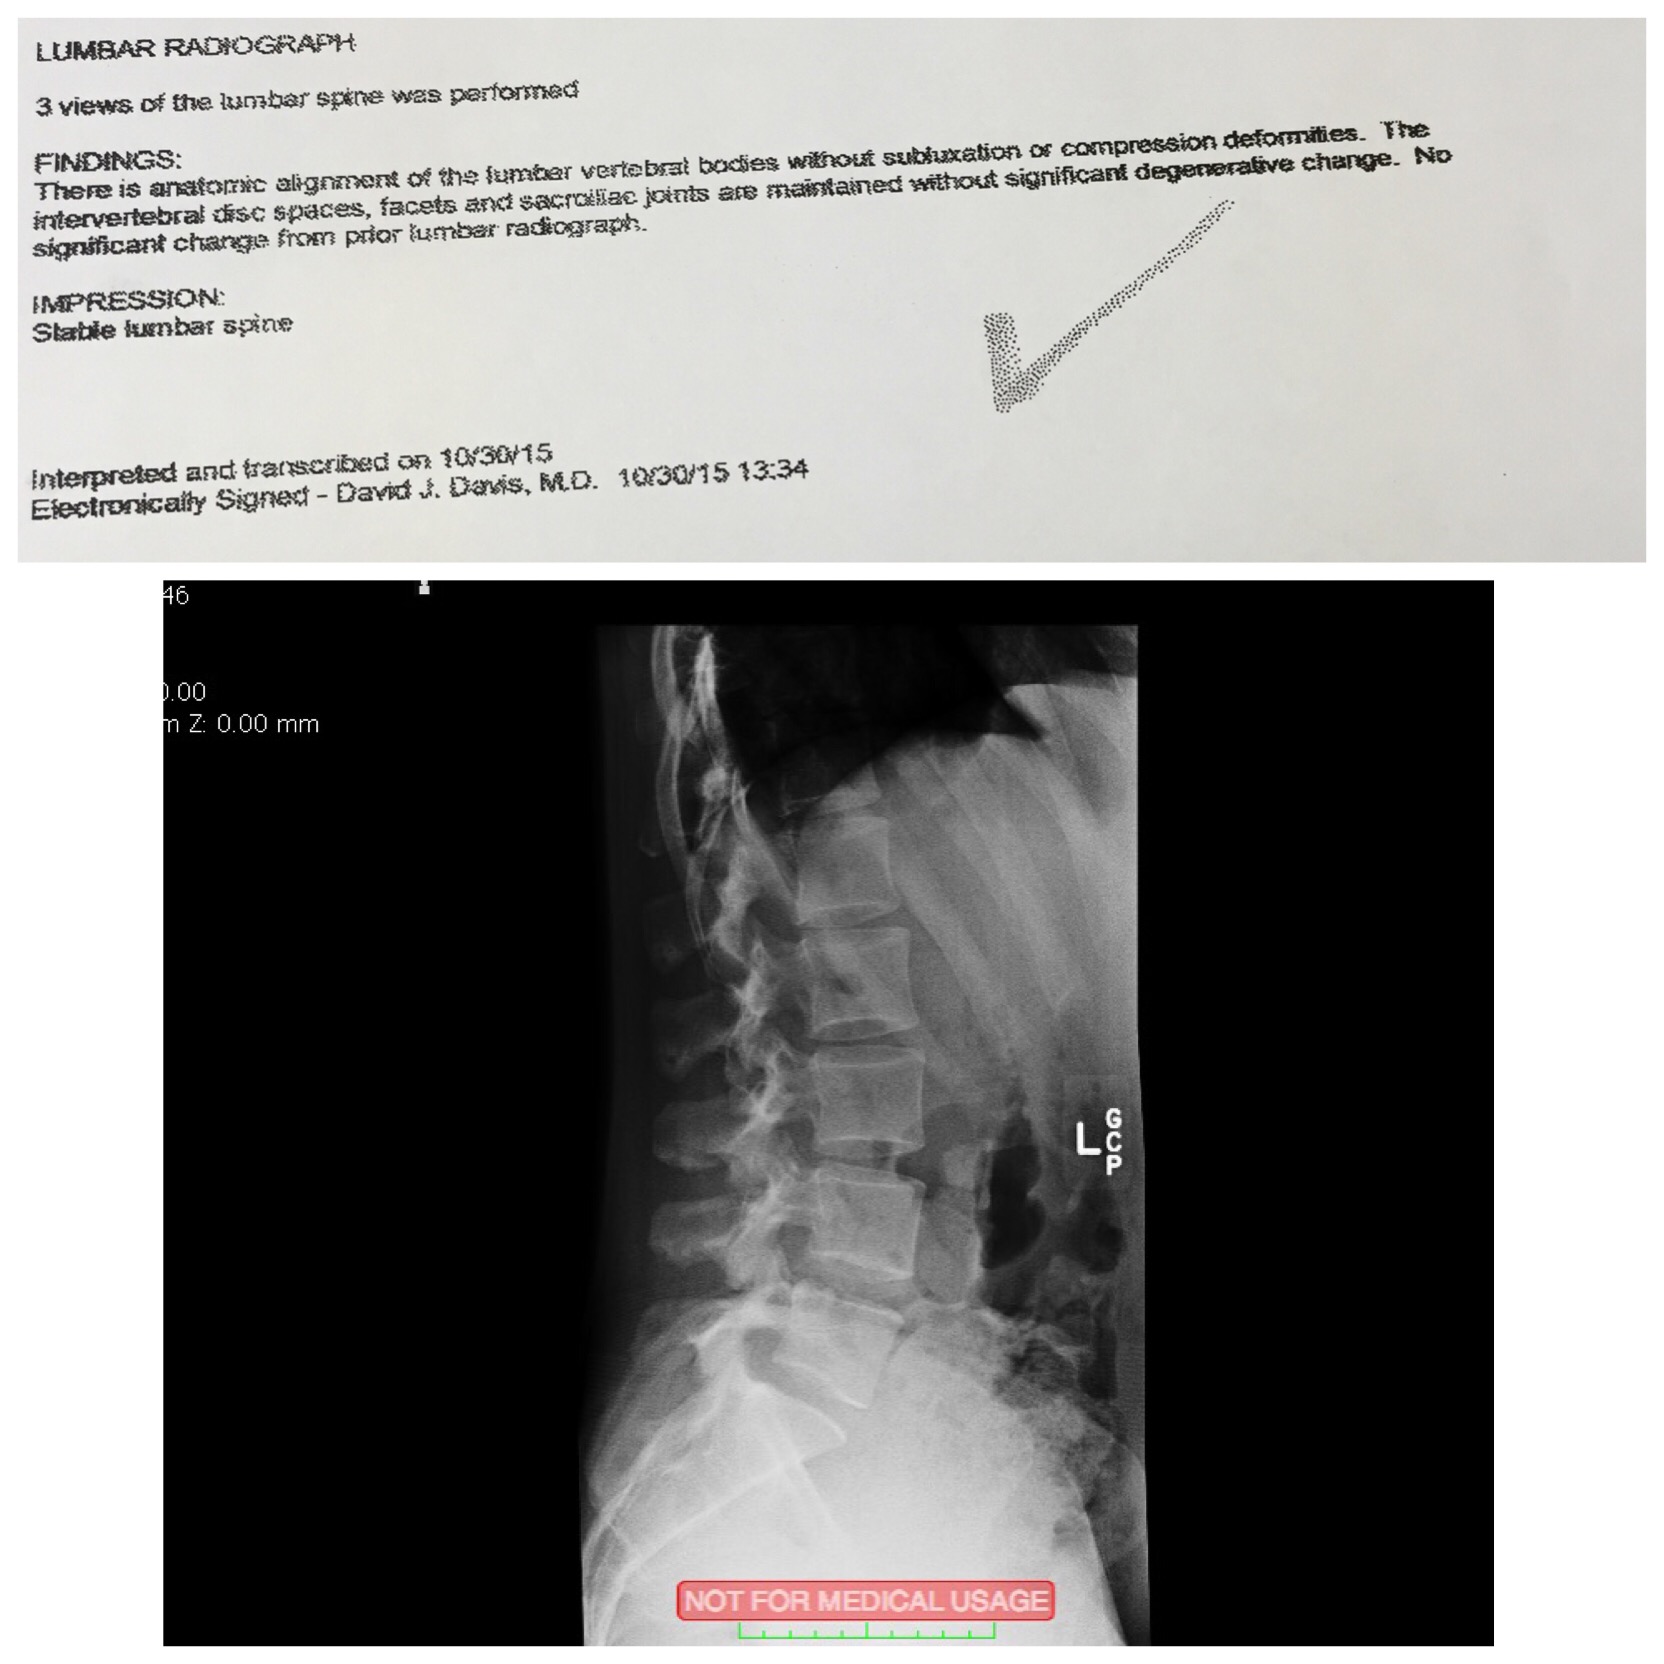

Today I received good news, after about 6 months from my MRI I did another X Ray on lower back to check the situation, for me it’s very important to know I train without hurting myself but optimizing my knowledge and time for a healthy productive training. The results were very positive, the L5-S1 regained more intervertebral space, reducing some tilting in the sacrum, which means more room for nerves and spinal cord 🙂 Correcting my training helped tremendously. You can see here: